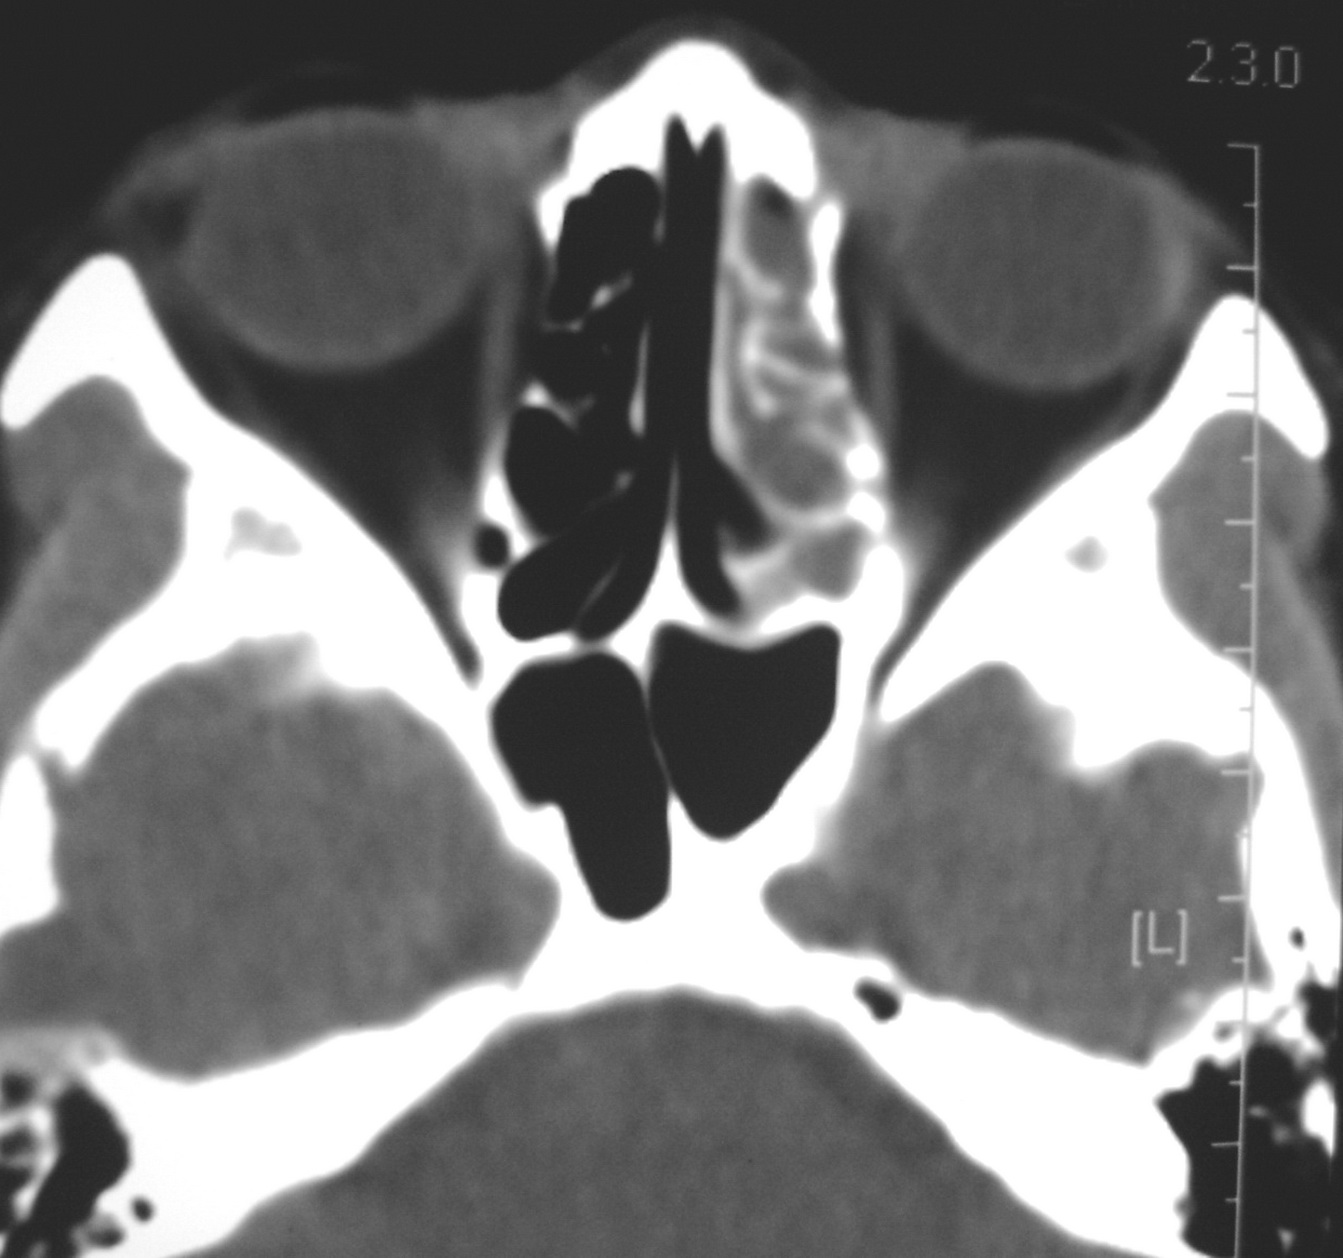

右侧眼眶脂肪瘤

女,34岁。右眼不适半年。

会员诊断:

表皮样囊肿、皮样囊肿、脂肪瘤

手术病理

:右侧眼眶

脂肪瘤

。